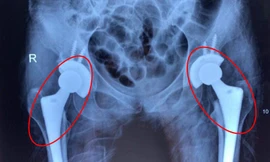

TPO - Tắc mạch máu diễn tiến âm thầm khiến nhiều bệnh nhân bị mục cả 2 khớp háng, đối mặt nguy cơ tàn phế. Bác sĩ cảnh báo, nguyên nhân dẫn tới tình trạng trên là do người bệnh lạm dụng rượu bia. Giải pháp để cứu bệnh nhân là thay cả 2 khớp háng.